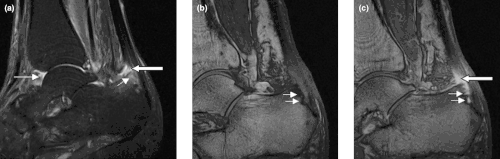

Sagittal magnetic resonance images of the ankle region in psoriatic arthritis. (a) Short tau inversion recovery (STIR) image, showing high signal intensity at the Achilles tendon insertion (enthesitis, thick arrow) and in the synovium of the ankle joint (synovitis, long thin arrow). Bone marrow edema is seen at the tendon insertion (short thin arrow). (b, c) T1 weighted images of a different section of the same patient, before (panel b) and after (panel c) intravenous contrast injection, confirm inflammation (large arrow) at the enthesis and reveal bone erosion at tendon insertion (short thin arrows). -